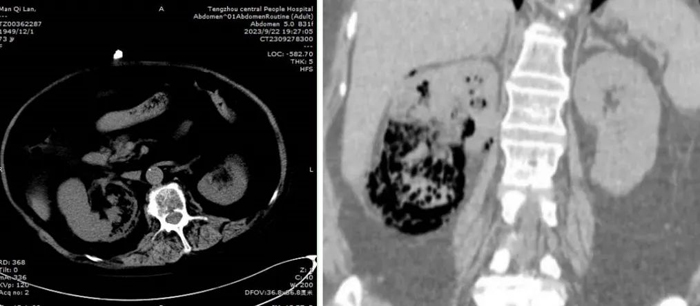

CT顯示右腎實(shí)質(zhì)積氣

滿阿姨轉(zhuǎn)入泌尿外二科后,單鋒芝副主任醫(yī)師組織科室討論,認(rèn)為患者有長(zhǎng)期服用糖皮質(zhì)激素,免疫力下降等誘發(fā)本病的危險(xiǎn)因素,經(jīng)CT檢查,診斷“氣腫性腎盂腎炎”成立,明確治療方案為抗菌素+內(nèi)置輸尿管支架引流+腎穿刺造瘺治療。